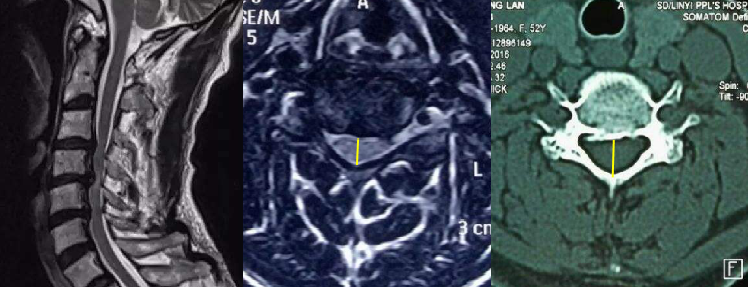

颈椎管狭窄分度:

颈椎X线侧位片或CT轴位测量

正常:正中矢状径≥14mm

相对狭窄:正中矢状径12-14mm

狭窄:正中矢状径10-12mm

绝对狭窄:正中矢状径≤10mm

颈椎矢状位可能清晰显示后纵韧带钙化、椎管狭窄、颈髓受压变性。但狭窄程度,具体程度,在轴位图像上测量会更准确。